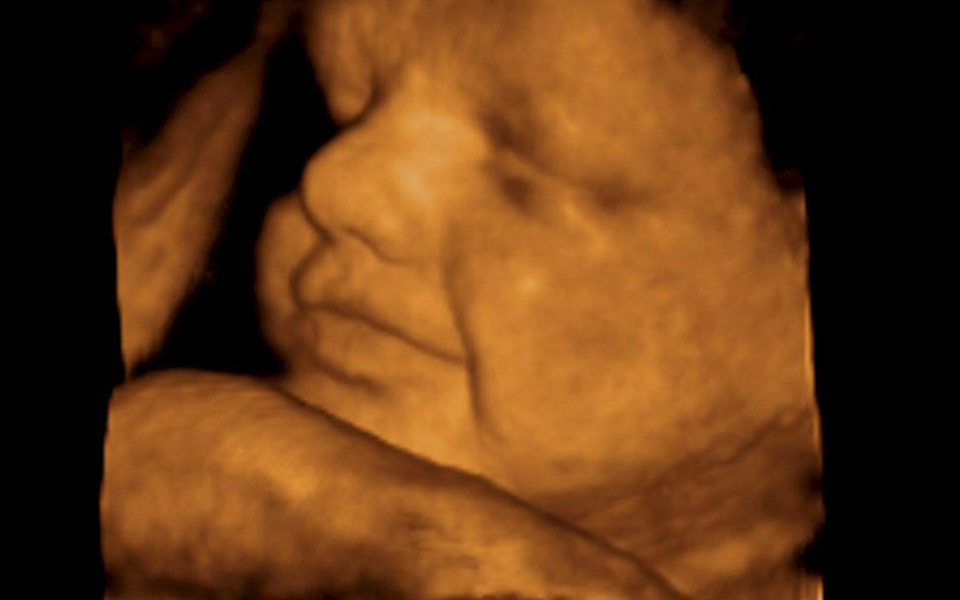

ΕΠΙΣΤΗΜΗ

Αυτιστικό παιδί θεραπεύθηκε